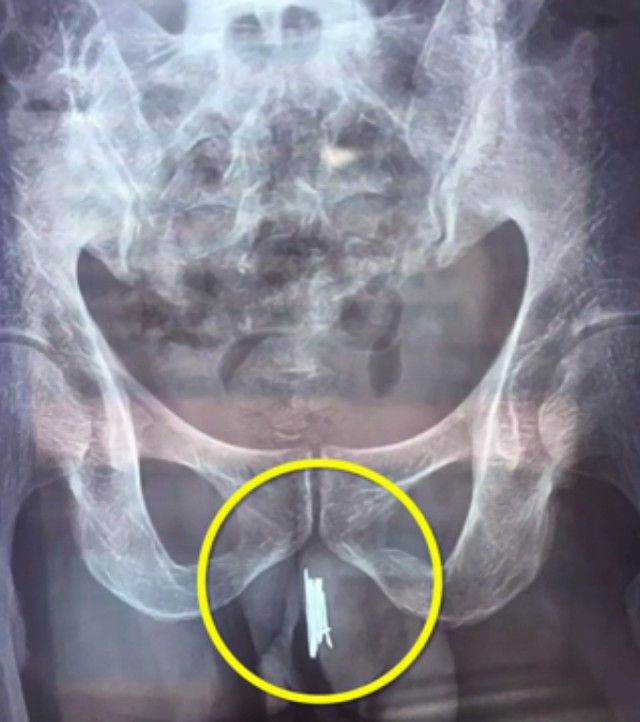

gif_animation 台湾にて、「尿道オナニー」にハマった男性(30歳)が長さ20cmのアダルトグッズを尿道に挿入、抜けなくなり病院へ運ばれたというニュース。アダルトグッズは膀胱にまで達していたそう…。(※ TOP画はイメージ)[5]images